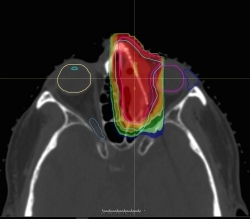

טכנולוגיית סריקת קרן העיפרון HYPERSCAN מספקת קצוות מינון חדים, ונותנת לקלינאים כלי מדויק להבאת טיפול פרוטונים למקומות רגישים. (תמונה: Business Wire)

בנוסף, HYPERSCAN PBS משתמשת במקבל (קולימטור) הפרוטונים מרובה העלים (pMLC) Adaptive Aperture™. הטכנולוגיה הזאת משתמשת במערכת הקבלה עם בקרה רובוטית, שמסוגלת לקצץ את קצות הקרן בכל שכבה של ביצוע. יכולת זאת מספקת ירידה עד פי שלושה חדה יותר בקרינה בקצה שדה הביצוע. זה משפר את אי הפגיעה ברקמות בריאות ומגביל קרינה לא נחוצה למקומות רגישים.